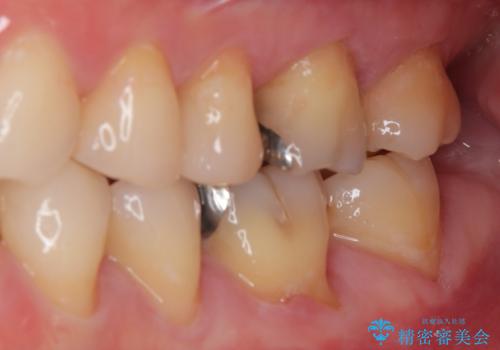

特に異常もなく見た目、噛み合わせともに満足していただけました。

ラバーダム防湿を行い、セラミックの接着をすることで、唾液や血液などの接着阻害因子を排除することができます。

歯と歯の間の虫歯をコンポジットレジンや保険のメタルインレーで治すと段差ができたりして清掃性が悪くなるので、セラミックインレー修復やゴールドインレー修復などの適合の良い詰め物で治療することをオススメします。